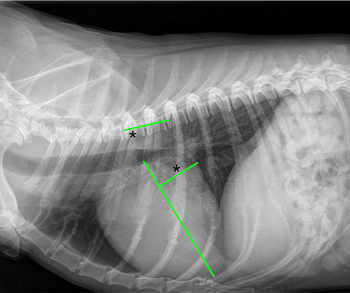

• VHS measurements to detect enlargement

The Vertebral Heart

Size or Scale or Sum (VHS) is an objective means of measuring

heart size.

As

the x-ray image above shows, using calipers, they

measure the length (from the apex to the bottom of the left mainstem) and width

(at

its widest point perpendicular to the lemgth measurement) of the heart

on a lateral x-ray and compare those dimensions

to the number of veterbrae from T4 to T12, to calculate the VHS value. Since

the dog's own vertebrae are used for comparison, each VHS value is

normalized to the dog's overall body size.

The VHS is not intended to diagnose CHF. It's purpose is to enable veterinarians to more accurately determine enlargement of the heart (called cardiomegaly or dilation) and the progression at which the enlargement is occurring, which usually is due to MVD. However, since MVD normally initially causes only the left atrium (LA) to enlarge, the VHS method is not precise enough to measure only the size of the LA. See for example, the x-ray at left, which shows that the VHS measurements entirely miss the bulbous enlarged LA in the upper right corner of the heart. (Image from Hezzell, 2018.)

An increase in VHS value of >0.1 per month over six months or more, in combination with a VLAS value >3.0, (see VLAS below) is evidence that the patient's heart has enlarged enough to classify it in Stage B2.